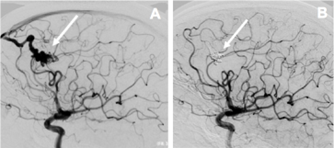

Les malformations vasculaires cérébrales (MAV) pouvant être responsables d’hémorragies cérébrales sont de plusieurs types. Cette cause est plus fréquente chez le sujet jeune. Les principales sont les malformations artério-veineuses cérébrales (connexion directe entre artères et veines sans interposition du lit capillaire) (Fig.1), les cavernomes (agglomérat sous forme d’une petite sphère bien délimitée de vaisseaux sanguins anormalement dilatés) et les anévrismes artériels cérébraux (dilatation localisée de l’artère).

Fig. 1 : Artériographie montrant une communication directe entre artère et veine (sans interposition d’un lit capillaire) (A) et sa guérison après embolisation de la malformation (B)